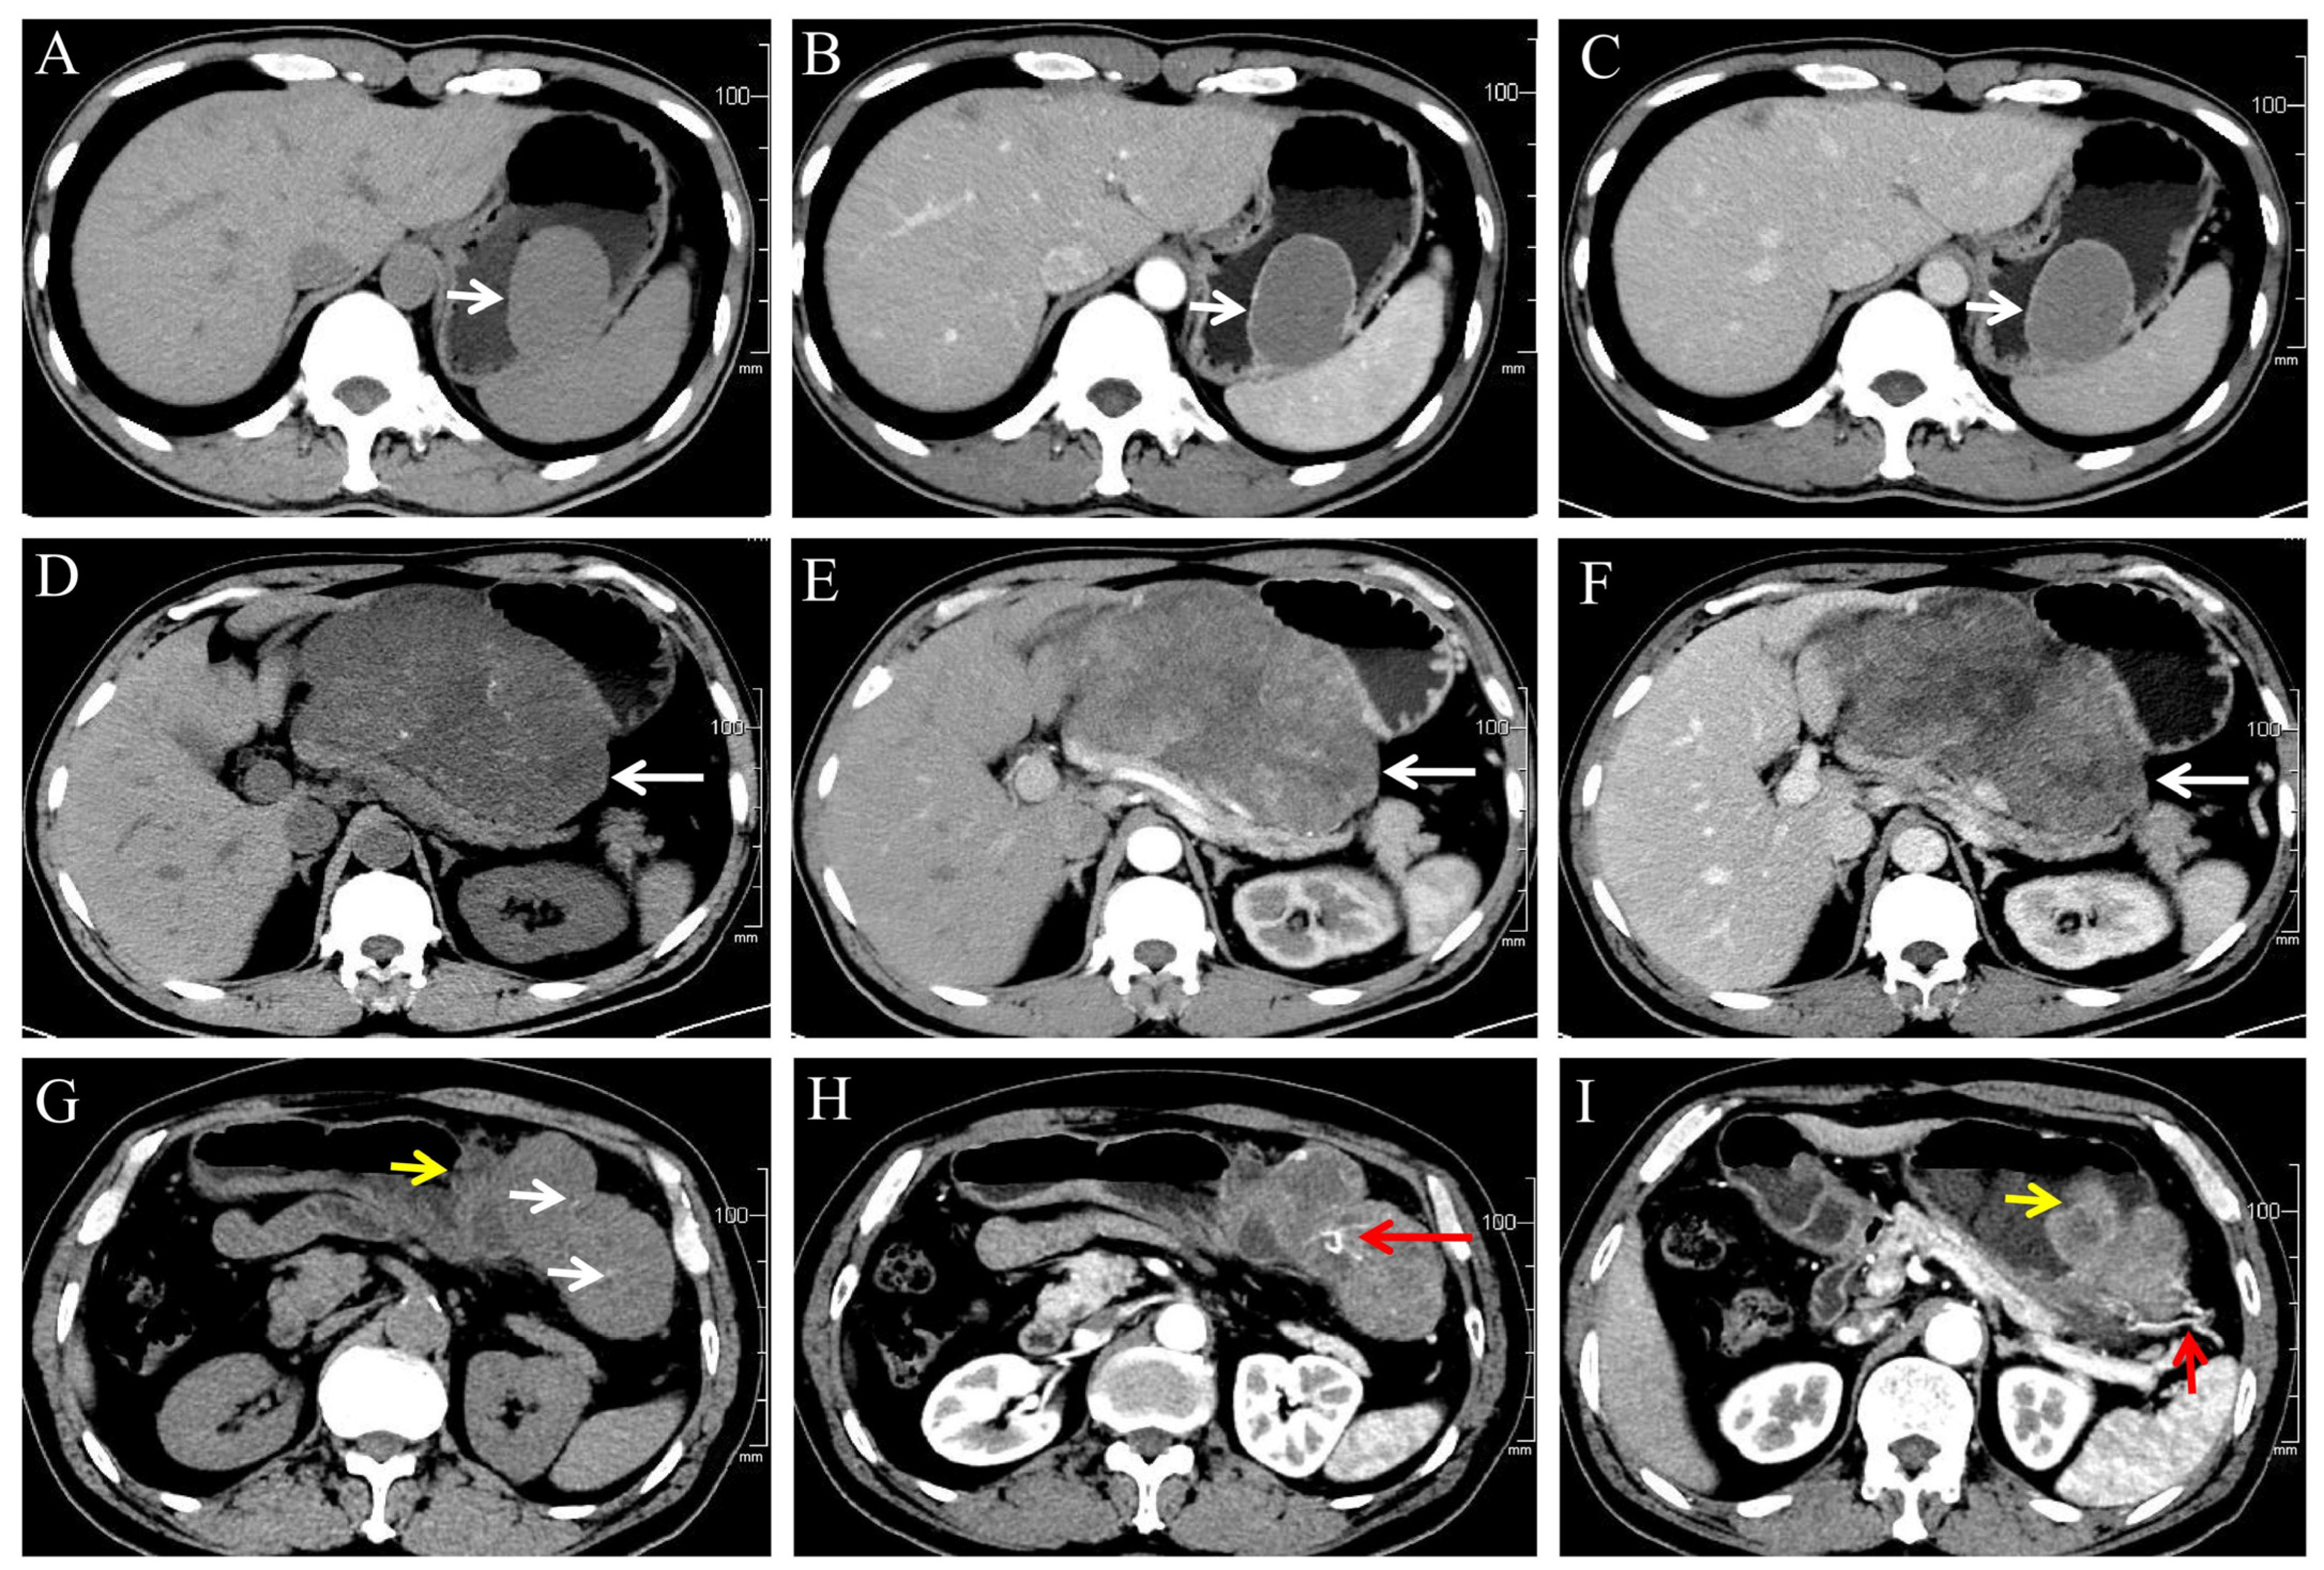

3.2. CT Features (Table 3, Figure 2)

Figure 2. (AC) A 46-year-old male patient with very low-risk GSTs in gastric body (white arrow). The non-contrast (A), arterial phase (B), and venous phase (C) CT images showed endophytic growth tumor with regular morphology, homogeneous enhancement and no necrosis. (DF) A 59-year-old male patient with moderate-risk GSTs in gastric body (white arrow). The non-contrast (D), arterial phase (E), and venous phase (F) CT images showed exophytic growth lesion with irregular morphology, thin dotted calcification (D), heterogeneous enhancement, and necrosis. (GI) A 57-year-old male patient with high-risk GSTs in gastric fundus. The non-contrast (G), arterial phase (H,I) CT images showed a mixed growth tumor with irregular morphology, thin dotted calcification ((G), white arrow), heterogeneous enhancement and necrosis area, feeding artery ((I), short red arrow), vascular-like enhancement ((H), long red arrow), and ulceration ((G,I), short yellow arrow).